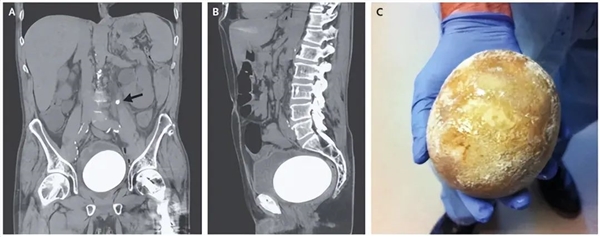

但斯里兰卡一名男子体内的肾结石达到了“葡萄柚”的尺寸,长13.37厘米,宽10.55厘米。

这个体积,远远超过他体内被“寄生”的肾脏,肾脏的长度只有11.8厘米。

重量更是大到难以想象,足足800克,差不多是一只8周大的小猫体重,有5个肾脏那么重。

无论是体重,还是体积,这颗结石都刷新了当时的世界纪录,两项都被载入2023年吉尼斯纪录中,成为吉尼斯世界纪录收录的众多项目中,非常特别的一个。

2023年6月1日,斯里兰卡医生为该男子做了去除肾结石的手术,手术很顺利,医生表示虽然肾结石比肾脏(右边)都要大,但取出后,他的右肾功能是正常的,其它身体方面也很正常。